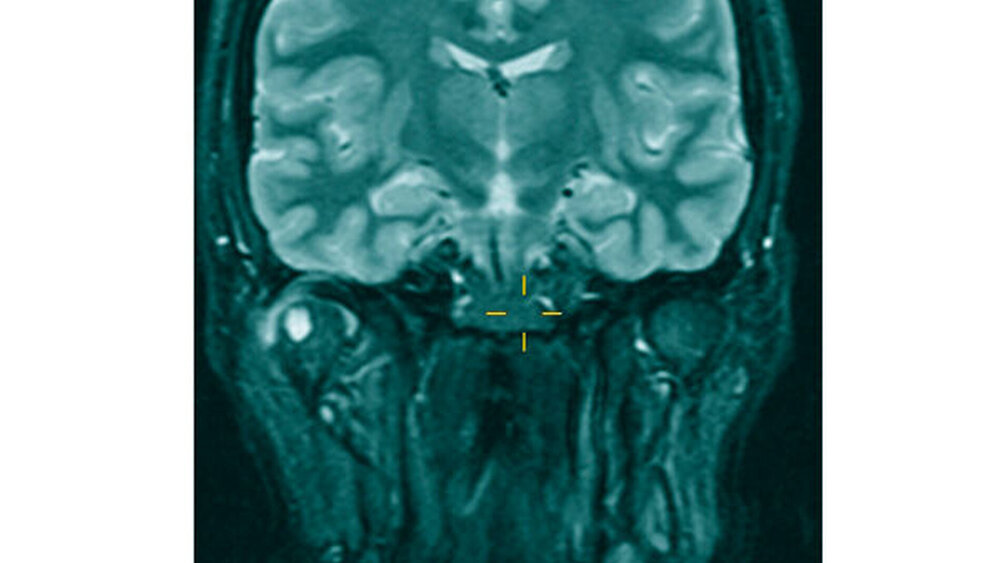

Im Rahmen der klinischen Untersuchung zeigte sich die sonografische Darstellung des Kiefergelenks und dessen angrenzender Strukturen als unzureichend, so dass zur weiteren Diagnostik eine Kontrastmittel-gestützte MRT-Untersuchung des Kiefergelenks eingeleitet wurde (Abbildung 1).

Beim bildmorphologischen Nachweis eines mäßigen Gelenkergusses mit irregulär verdickter, vermehrt Kontrastmittel aufnehmender Synovia, einer ventral gelegenen 2,2 cm x1,3 cm messenden, T2-hyperintensen Läsion mit tubulärer Verbindung zum Gelenkkavum sowie einer 6 mm durchmessenden zystischen Läsion mit randständigem Kontrastmittel-Enhancement im rechten Mandibulaköpfchen ergab sich der differenzialdiagnostische Verdacht auf eine Gicht, eine Pseudogicht oder eine Erkrankung aus dem rheumatoiden Formenkreis.